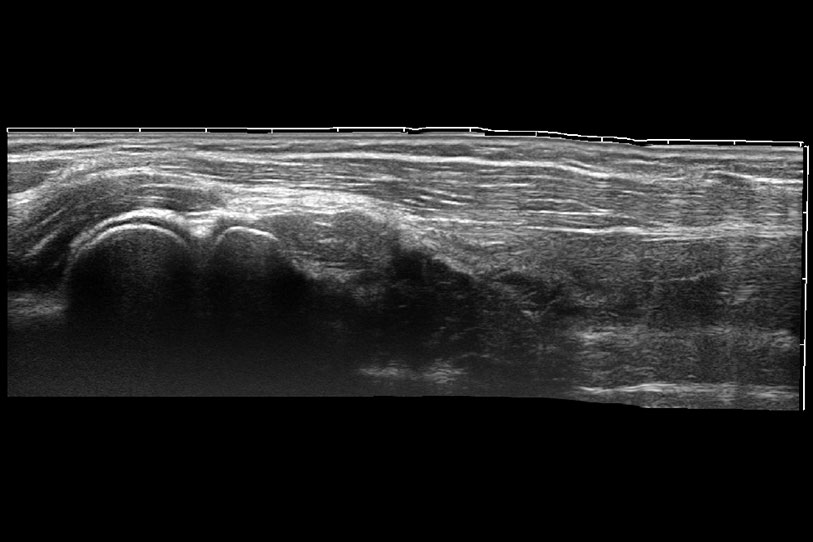

通過(guò)色彩血流和實(shí)時(shí)寬景相結(jié)合,可觀察到完整的靜脈或動(dòng)脈的血流,方便醫(yī)生檢查。實(shí)時(shí)掃查過(guò)程中,如有任何操作失誤也可以很容易地進(jìn)行回掃擦除,而不會(huì)中斷掃查。